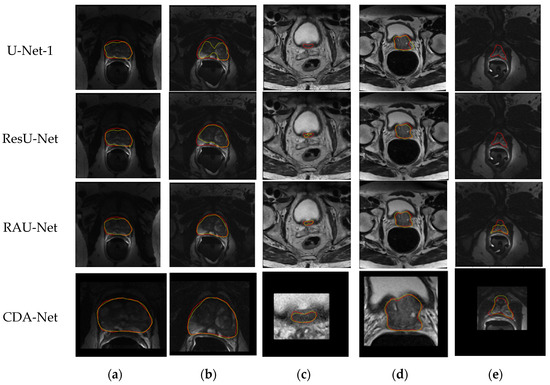

In addition, in order to further intuitively present the segmentation performance of the algorithm, we visually displayed and compared the predicted segmentation and ground truth of the above four algorithms. The comparison results are shown in Figure 10, where the red line marks the actual contour of the organ, the yellow line marks the outline of the predicted segmentation result obtained by the algorithms, and the fourth row is the segmentation result after ROI cropping.

Since slice images with high imaging quality and clear organ contours have almost achieved perfect segmentation performance in many segmentation algorithms, especially those based on deep learning, this paper does not involve much of such images. As shown in Figure 10,

• The first column compares the segmentation performance of each algorithm in the images with endorectal coils. It can be seen that the four algorithms based on the U-Net architecture are not excessively affected by coil artifacts and image contrast, and they have achieved relatively good performance;

• The second column shows the performance of the four algorithms when the gray distribution inside the gland is obviously uneven. We can see that the predicted segmentation results of the U-Net-1 and ResU-Net algorithms are affected to varying degrees at this time. In contrast, the contours obtained by the RAU-Net and CDA-Net proposed in this paper can still have a good matching effect with the real segmentation contour, which fully reveals that the attention gate mechanism added in this paper can have a more accurate estimation of attention to the region where the organ is located, thereby guiding the algorithm to obtain a more reasonable segmentation result;

• Besides, columns 3–5 specifically compare the segmentation performance of the algorithm on the apex and base of the slice sequences. It can be observed that the proportion of organs in the slice images at both ends of the organ is very small, and the contours of the organs in the base slices are often blurred. Therefore, this is usually the most challenging part of prostate segmentation, and it is also the key part that can distinguish the performance of the algorithm. Comparing the segmentation results of the four algorithms in the third and fourth columns, we can see that the algorithms ResU-Net and RAU-Net can better obtain the position of the organs than U-Net-1, but the accurate segmentation of the organs is still inferior to CDA-Net;

• Similarly, in the fifth column, even though the organs are relatively small and the contours are irregular, the algorithm CDA-Net in this paper still achieves a better segmentation performance than the first three algorithms. It demonstrates that the initial ROI extraction based on the sequence correlation used in this paper can effectively locate the organ position, thereby greatly reducing the focus of subsequent fine segmentation, and making the CDA-Net algorithm present more significant advantages in the segmentation of prostate base and apex.

Figure 10. Qualitative comparison results of the algorithms on the test set from PROMISE12 (the red line masked the true contour of the prostate and the green line masked the contour obtained by the algorithm; (a) the images with ERC; (b) the image with an uneven gray distribution of glands; (c) the images at the base of sequences; (d) the images at the base of sequences with irregular organ shapes, (e) the images at the apex of sequences.